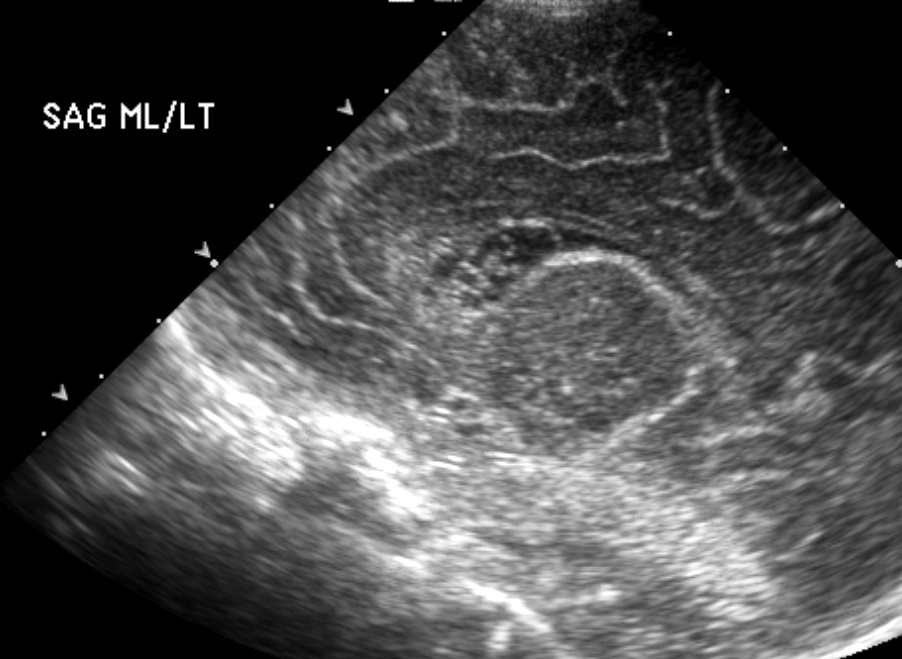

Info Images Findings Impression Reco/Acuity Case Images View Images / Launch Visage Case Notes History Full term infant. We are asked to evaluate posterior fossa cyst. Exam Gray scale and Doppler Ultrasonographic examination of the head. Prior Study N/A Dicom View Reference Material

Section 1 Submit Findings Case149 Findings Brain The brain is immature. Yes No There is under-sulcation and open sylvian fissures. Yes No There is/are multiple hypoechoic areas in the periventricular white matter. Yes No There is/are multiple hyperechoic areas in the periventricular white matter. Yes No There is diffuse cerebral edema with diffusely increased echogenicity of the brain parenchyma and loss of grey white matter differentiation. Yes No The thalami/basal ganglia are hypoechoic. Yes No There is periventricular calcification. Yes No There is intra-parenchymal calcification. Yes No CSF spaces/ventricular system There is a prominence of the extra axial fluid spaces. Yes No There are debris/septations in the extra axial fluid spaces. Yes No There are debris/septations in the ventricles. Yes No There is a subdural collection on the right/left side. Yes No There is prominence of the ventricular system. Yes No There is an asymmetry of the ventricular system. Yes No There is a cavum septum pellucidum. Yes No There is a midline shift towards right/left. Yes No The choroid plexus is bulky/lobulated. Yes No There is a choroid plexus cyst measuring… Yes No There are debris/clots in the occipital horn. Yes No There is a posterior fossa cyst measuring… Yes No The tentorium is elevated/depressed. Yes No The lateral ventricle/s are dilated. Yes No The third ventricle is dilated. Yes No The 4th ventricle is dilated. Yes No There are pseudo cysts. Yes No Germinal matrix hemorrhage (Only in the premature infants): Please do not answer if the patient is a full term. There is a germinal matrix hemorrhage, consistent with a grade I hemorrhage. Yes No There is an intraventricular extension consistent with a grade II hemorrhage. Yes No There is an intraventricular extension with the dilatation of ventricles, consistent with a grade III hemorrhage. Yes No There is an intra-parenchymal extension, consistent with grade IV hemorrhage. Yes No On color Doppler examination, the Resistive index in the anterior cerebral artery is… There is a loss of the diastolic flow on the Doppler exam. Yes No There is altered vascularity on Doppler imaging. Yes No There is an AVM in the region of… Yes No